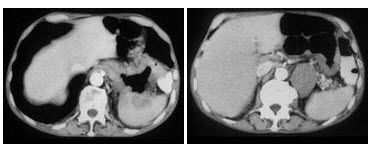

153、多项选择题

男,48岁,蛋白尿多年,CT如图所示,最可能的诊断为肾静脉血栓,肾静脉血栓形成的原因是()

A.膜性肾小球肾炎

B.肾癌

C.胰腺炎

D.外压性

E.创伤、脱水、血小板增多症